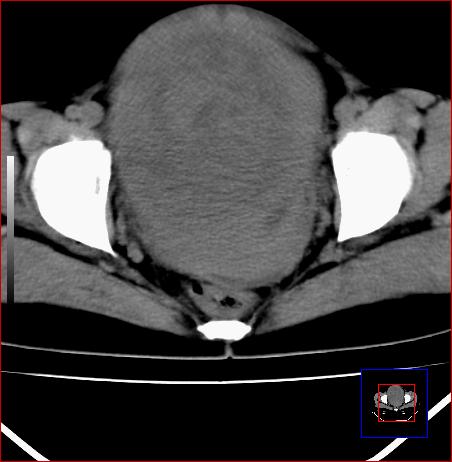

标题: CT15141:子宫肌瘤还是卵巢肿瘤 [打印本页]

腹部包块1年余,近两月明显增大,月经量多

子宫肌瘤?子宫内膜ca?建议进一步检查。

与子宫关系密切,子宫肌瘤/子宫癌。

子宫体积增大,内密度不均匀。边缘清晰。考虑子宫肌瘤可能性大。